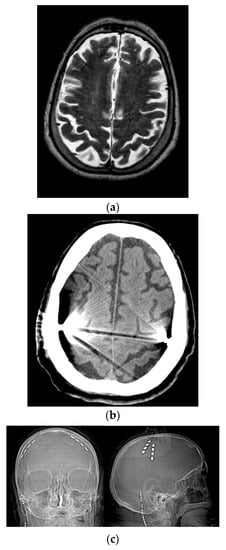

The surgical procedure was performed with patients under total intravenous anesthesia: a quadripolar electrode strip (model Resume; Medtronic Inc, Minneapolis, Minnesota) was epidurally placed over M1 (through a burr hole over, contralateral to the most affected body side in three patients and bilaterally in remaining patients) and connected to a Soletra or Kinetra (Medtronic Inc) implantable pulse generator (IPG) located in the subclavian region. In all patients, contacts were oriented along the craniocaudal axis of the precentral gyrus: contact 3 was 2 to 3 cm from midline, contact 0 was 4 cm more lateral (Figure 1). Implantation site was preoperatively defined (using magnetic resonance imaging and neuronavigation) and verified by means of motor-evoked potentials and by identifying N20-P20 phase reversal of somatosensory evoked potentials obtained from contralateral median nerve stimulation [22]. Patients postoperatively underwent a computed tomography scan to confirm that the electrode paddle was correctly placed and to rule out surgical complications.

Figure 1. Placement of quadripolar electrode strips over the motor cortices. (a) Preoperative brain MRI. (b) Postoperative brain CT scan. (c) Postoperative skull X-ray. R = right; L = left.